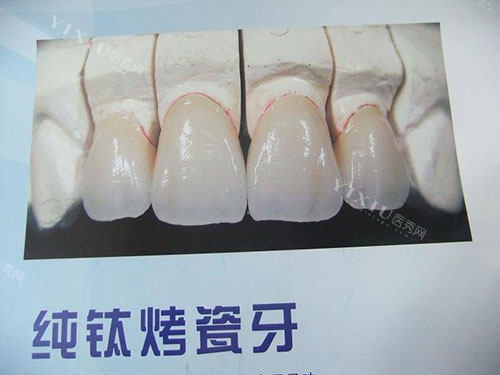

钴铬合金烤瓷牙

前面提到的2000元起的含钴铬内冠烤瓷牙,性价比很高。钴铬合金烤瓷牙具有较好的生物相容性,价格相对亲民,适合大多数对牙齿修复有需求的人群。它能在一定程度上改善牙齿的形态和功能,在普通的牙齿修复术例中应用广泛。